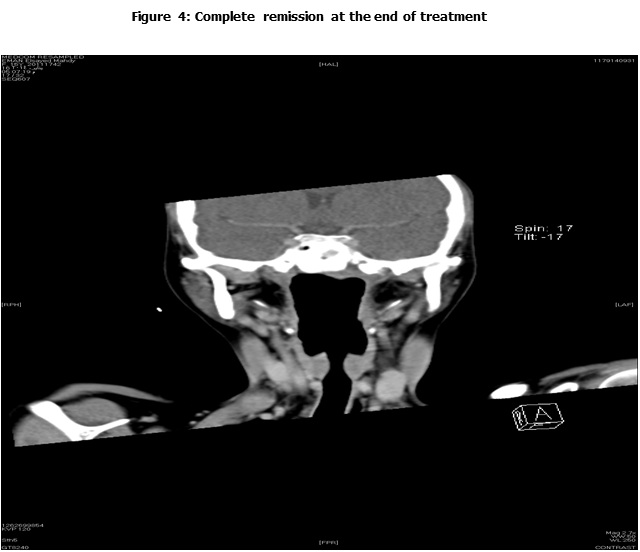

Tumor response was evaluated using the modified version of the Response Evaluation Criteria in Solid Tumor (RECIST) which included volumetric measurement of the primary NPC, and assessment of associated adenopathy. Measurable and non-measurable metastatic foci in the lungs, bones and liver were also evaluated9.

Complete Response (CR): complete disappearance of the tumor confirmed.

Response to Treatment:

Following induction chemotherapy, the overall response rate (CR and PR) was seen in 19 patients (73%); (4 patients (15.3%) achieved CR, 15 (57.6%) PR. Five patients (19.3%) had SD and 2 patients (7.7%) had PD. Whereas, at time of final analysis, 18 patients (69.2%) achieved CR, 5 patients (19.2%) had PD (4 deaths (15.3%), and 1 patient (3.8%) alive under palliative treatment), and 3 patients (11.5%) lost follow up. Table 2 describes patient's response to therapy.